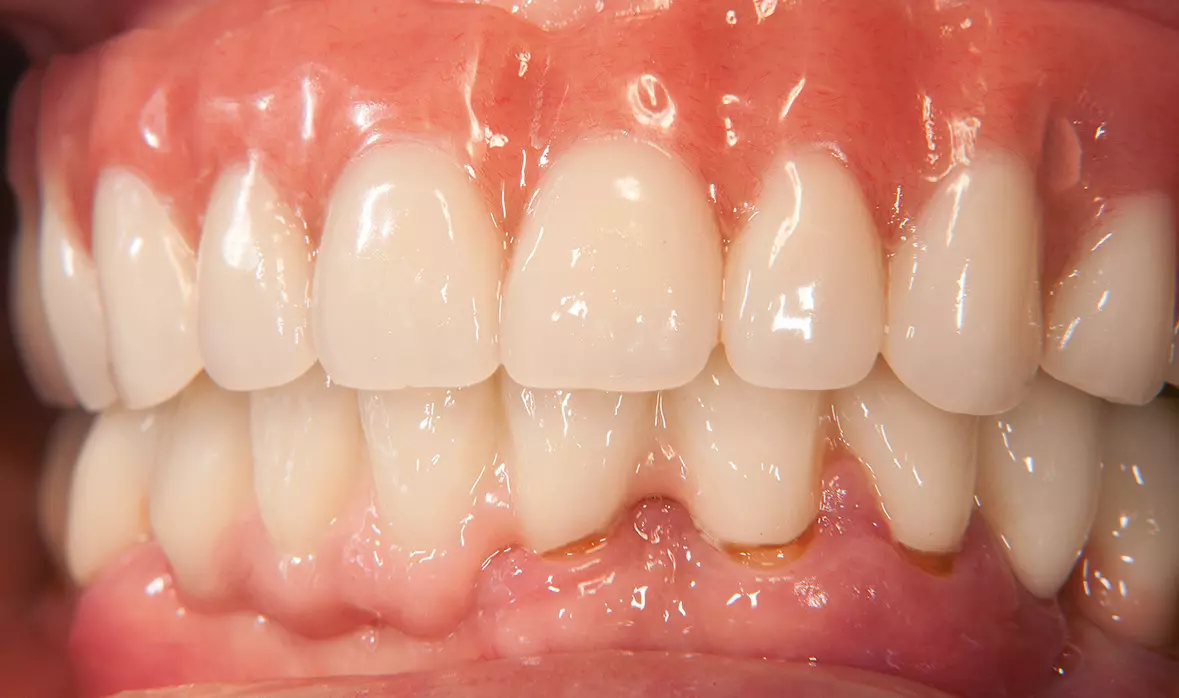

Abb. 44: Fertige Prothese im Mund. Dr. Michael Leistner

Abb. 44: Fertige Prothese im Mund.

Abb. 45: Laterale Ansicht. Dr. Michael Leistner

Abb. 45: Laterale Ansicht.